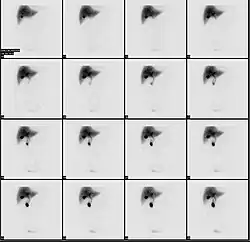

Normal hepatobiliary scan (HIDA scan). The nuclear medicine hepatobiliary scan is clinically useful in the detection of the gallbladder disease.

Normal hepatobiliary scan (HIDA scan). The nuclear medicine hepatobiliary scan is clinically useful in the detection of the gallbladder disease. -